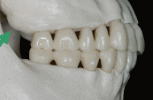

6.上顎歯列弓の側方限界

![]() |

下顎歯列弓の大きさ・形態 |